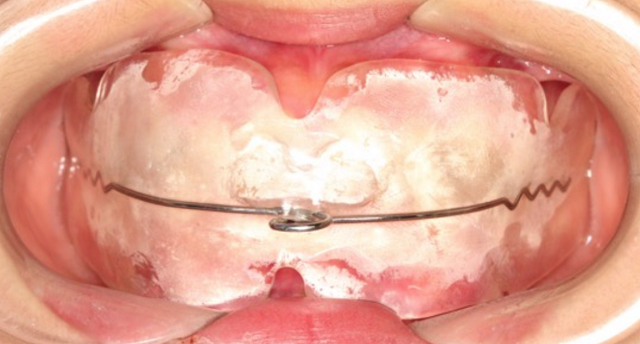

黃丞一副主任醫(yī)師仔細(xì)檢查后發(fā)現(xiàn),孩子的門牙突出,上頜牙弓特別狹小,整排牙齒都非常不整齊。

“當(dāng)腺樣體組織異常增生肥大時(shí),就會(huì)堵塞氣道,導(dǎo)致長(zhǎng)期張口呼吸,還可影響頜面部發(fā)育,形成特殊的腺樣體面容。腺樣體面容是指由于腺樣體肥大導(dǎo)致牙齒不整齊并且向外凸出,形成齙牙,上嘴唇也會(huì)變厚,腭骨高拱,還伴有表情呆滯等情況!秉S丞一醫(yī)生說(shuō)。

雖然當(dāng)時(shí)接診時(shí),小林的腺樣體腫大已經(jīng)存在了一段時(shí)間,不過(guò)幸好發(fā)現(xiàn)及時(shí)。根據(jù)黃醫(yī)生的建議,小林及時(shí)到耳鼻喉科做了腺樣體摘除術(shù),并且認(rèn)真地進(jìn)行肌功能訓(xùn)練,對(duì)已經(jīng)凸出的牙齒進(jìn)行矯正。

第三,如果已經(jīng)發(fā)生了口腔錯(cuò)合畸形,就需要根據(jù)不同的錯(cuò)合畸形類型進(jìn)行功能性矯正和后期的固定矯正了。